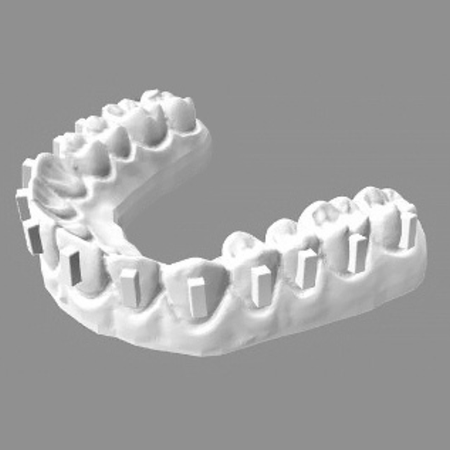

O efeito do uso de lupas odontológicas na precisão dos attachments de alinhadores e na área de adesivo remanescente após a colagem

Objetivo: Este estudo teve como objetivo avaliar se o uso de lupas odontológicas melhora a precisão na colagem de attachments em alinhadores e reduz a quantidade de resina remanescente após a colagem. Métodos: Seis modelos impressos...